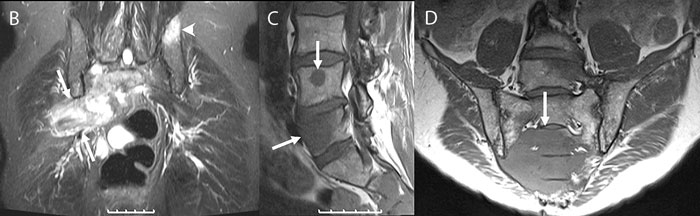

Figur 1. En 59-årig man, opererad och strålbehandlad 4 år tidigare för halstumör (röd flagga!) sökte på grund av värk i höger klinka ut mot höftleden. Han behandlades med antiflogistika och sjukgymnastik utan effekt. Vilovärk och sömnsvårigheter (röd flagga!) tillkom; B-SR 42 mm. Röntgen ländrygg, bäcken och höger höftled (A) visade degenerativa förändringar med fasettledsartros i nedre ländryggen men inga maligna förändringar. Besvären fortsatte och patienten sjukskrevs; 3,5 månader efter första remissen utfördes MRT ländrygg och bäcken. Denna visade på koronal STIR-sekvens en stor högsignalerande tumör som fyllde ut foramen ischiadicum majus på höger sida (B, pilar) samt en meta­stas i vänster os ilium (B, pilhuvud). På T1-viktade sekvenser sågs lågsignalerande metastaser i L4 och L5 (C, pilar) samt i sakrum (D, pil).